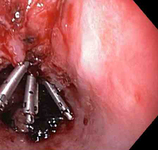

Mallory-Weiss tear

Three through-the-scope clips deployed to complete closure of the mucosal defect

From the collection of Juan Carlos Munoz, MD, University of Florida